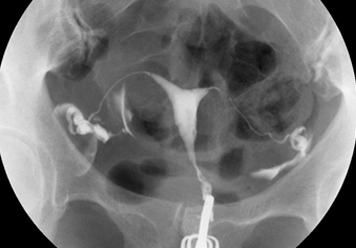

УДАЛЕНИЕ ПОЛИПОВ МАТКИ

И ЦЕРВИКАЛЬНОГО КАНАЛА